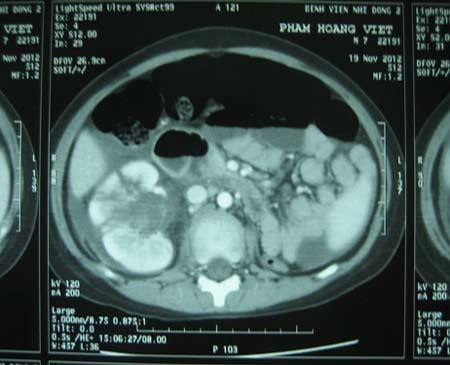

Trước đó, ngày 18/11, Việt đang đi xe đạp thì bị xe máy tông vào lưng. Sau khi té, bé thấy đau vùng hông phải, tiểu ra máu. Việt được chuyển đến BV Nhi Đồng 2 trong tình trạng vùng hông phải bầm tụ máu, ấn đau và tiểu ra máu. Sau khi làm CT và siêu âm bụng cho Việt, các bác sĩ phát hiện bé chỉ có một quả thận. Trái thận này bị chấn thương độ V, nứt làm 3 mảnh nhưng cuống mạch máu thận vẫn còn.

![]() |

| Hình ảnh siêu âm cho thấy bé Việt chỉ có 1 quả thận |